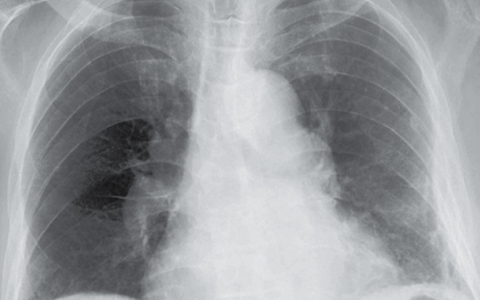

An 84-year-old man with benign prostatic hyperplasia who had been admitted to the hospital with acute kidney injury due to obstructive uropathy was noted to have gray skin. The skin changes had been present for 5 years. On physical examination, diffuse slate-gray pigmentation of the skin, particularly on the face, hands and nails, and sclera, was seen. A skin biopsy revealed small, dark granules in the basement membrane of sweat glands and in pilosebaceous units, blood vessels, and elastic fibers in the dermis. What is the diagnosis?

血清银水平为423纳摩尔每升(参考值,<10)。诊断为全身性银质沉着症。全身性银质沉着症是由系统性银暴露引起的,导致皮肤色素沉着不可逆地变暗。肤色变化在阳光暴露的区域最为明显,因为阳光催化了元素银的还原。患者在他几十年的服务员工作中没有显著的银暴露。他没有使用含银的产品,比如胶体银。他公寓楼里其他居民也没有肤色变化。出院时,患者被推荐进行进一步的毒理学评估。最终,银暴露的来源没有被识别。